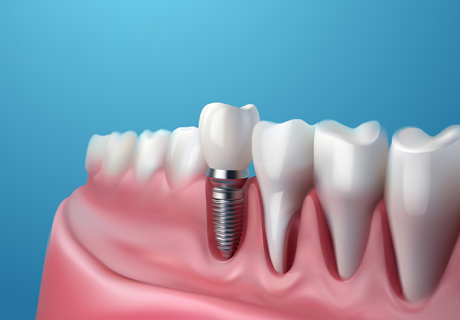

2개에서 4개 정도의 임플란트를 심고,

그 위에 딱 맞게 고정되는 틀니를 끼우는 방식입니다.

틀니 안쪽에 작은 고정장치가 있어

단추처럼 임플란트에 ‘딸깍’하고 끼워지는 구조라

일반 틀니보다 훨씬 덜 흔들리고 안정감이 좋습니다.